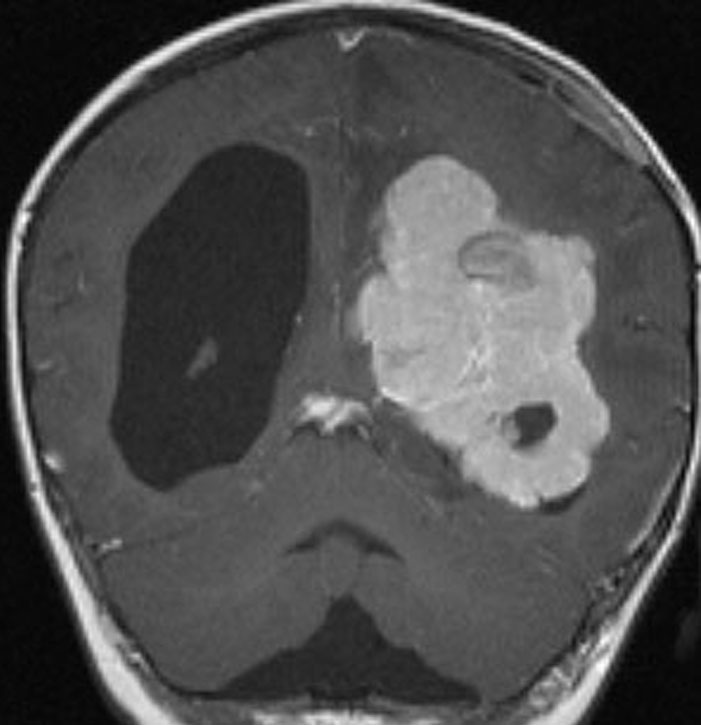

側脳室三角部に発生した大きな脈絡叢乳頭腫です。周囲に脳浮腫が高度なのですが,これでもグレード1です。大きくなると腫瘍血流が増えて,静脈鬱滞が生じて良性の乳頭腫でも腫瘍周辺脳浮腫を呈します。脳との境界が明瞭なところが脈絡叢癌との違いでもあります。